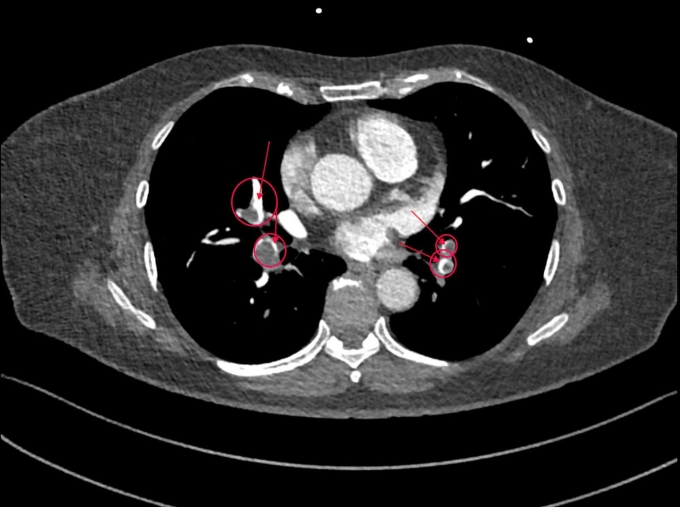

Kỹ thuật Triple Rule Out được thực hiện dưới sự hỗ trợ của hệ thống máy CT Somatom Force VB30 phát hiện huyết khối xuất hiện ở nhiều nhánh động mạch phổi (khoanh đỏ). Ảnh: Bệnh viện Đa khoa Tâm Anh

Bác sĩ Long giải thích kỹ thuật Triple Rule Out thường được áp dụng trong trường hợp người bệnh có biểu hiện khó thở, đau ngực không điển hình. Phương pháp này cho phép loại trừ nhanh những nguyên nhân nguy hiểm như nhồi máu cơ tim, bóc tách động mạch chủ, phát hiện huyết khối thuyên tắc phổi để can thiệp phù hợp.